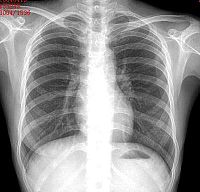

医学影像学在医学诊断领域是一门新兴的学科,不过目前在临床的应用上是非常广泛的,对疾病的诊断提供了很大的科学和直观的依据,可以更好的配合临床的症状、化验等方面,为最终准确诊断病情起到不可替代的作用;同时也很好的应用在治疗方面。

医学影像学Medical Imaging泛指通过X光成像(X-ray),电脑断层扫描(CT),核磁共振成像(MRI), 超声成像(ultrasound),正子扫描(PET),脑电图(EEG),脑磁图(MEG),眼球追踪(eye-tracking),穿颅磁波刺激(TMS)等现代成像技术检查人体无法用非手术手段检查的部位的过程。

主要包括X光成像仪器、CT(普通CT、螺旋CT)、正子扫描(PET)、超声(分B超、彩色多普勒超声、心脏彩超、三维彩超)、核磁共振成像(MRI)、心电图仪器、脑电图仪器等。

诊断主要包括(透视、放射线片、CT、MRI、超声、数字剪影、血管照影)。